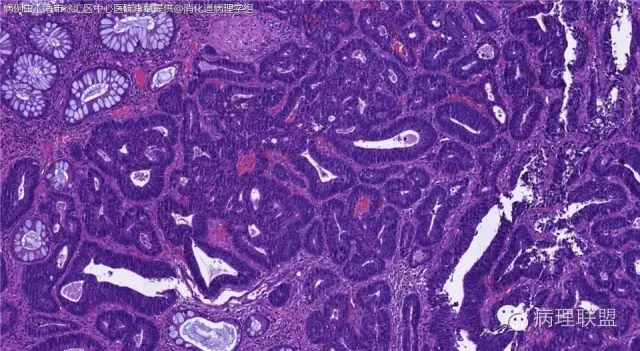

男,72岁,距肛门口30cm息肉。大体:灰白结节1.5*1*0.8cm拟发管状腺瘤并部分区高级别,请各位老师指导!(病例由上海市徐汇区中心医院 李斌 提供,致谢!)

这一例有两种不同看法,按WHO标准,为高级别,按实际工作,要发粘膜内癌。WHO第三版与第四版均提出,侵犯至粘膜下层才能诊断为癌,声称结直肠粘膜内没有淋巴管,发生转移的概率较小,但是粘膜内有血管,肿瘤侵出粘膜腺体基膜以外,就能侵犯血管,照样可以发生血道转移。文献报告与我们的工作实践,发现腺瘤、高级别(没有侵出基膜)的患者,同样有发生血道转移。因此,我们废弃了这一条WHO标准(不是所有的WHO标准都是一定要执行的)。只要异型增生腺体呈毛刺状、迷芽状侵出粘膜腺体基膜,位于粘膜肌层以内,就发粘膜内癌。

@李斌 结肠腺瘤这例我认为已经有黏膜下浸润了,因为有些腺体间的间质已经不是固有膜间质而是促结缔组织增生反应的间质了。但即使有浸润癌,如果息肉完整摘除、癌成分分化好、没有脉管瘤栓、浸润癌距切缘大于1mm(日本标准还要看浸润癌超出黏膜肌深度和肿瘤出芽情况),也不需要进一步治疗。所以,对于这类可能存在争议的病变,特别是息肉已经完整切除的病例,诊断的关注点就应该放在寻找需不需要进一步治疗的证据上了。@邓永键 2010版WHO在腺瘤部分的陈述中已经写出对于有局灶浸润性生长的病例也可以称黏膜内癌,他们在悄悄的让步。